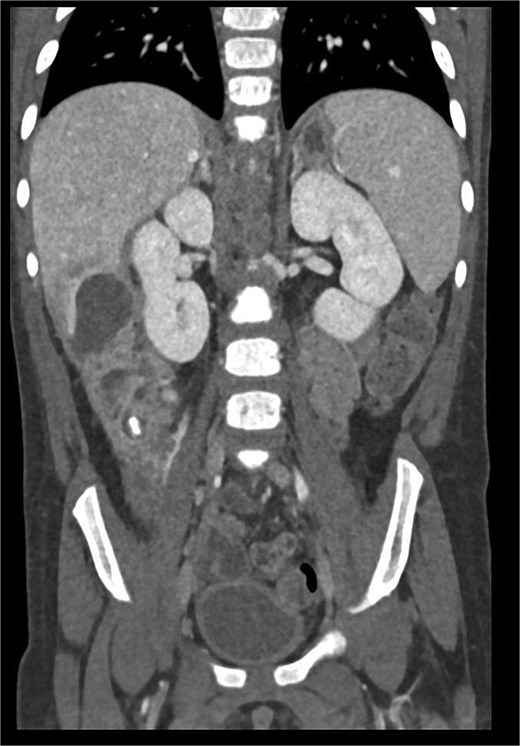

Abdominal ultrasonography identified a pathological, dense fluid collection in the right upper quadrant measuring 44 × 33 × 45 mm, located adjacent to segment VI of the liver (Fig. 1). The findings suggested an inflammatory lesion, possibly a hepatic abscess secondary to appendicitis with an atypically directed appendix. Empiric treatment with third-generation cephalosporins and metronidazole was initiated.

Abdominal ultrasonography imaging of pathological dense fluid collection adjacent to liver segment VI.